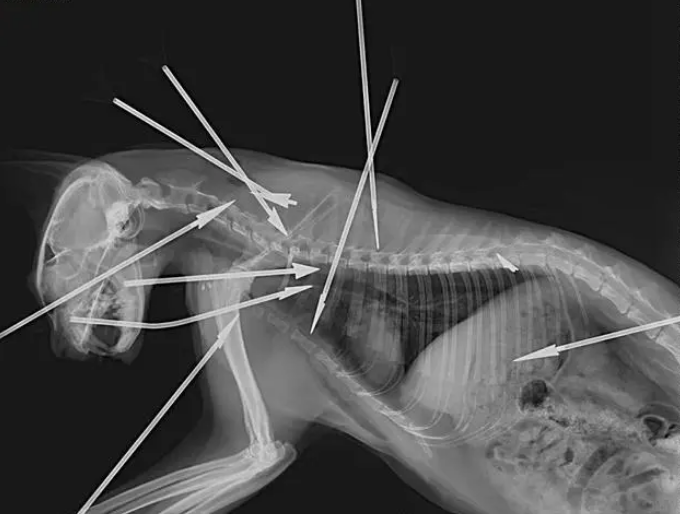

8月13日,杭州余杭区某小区居民发现,一只在小区生活了约3年的狸白猫被箭射伤,身上插着9支箭。14日,志愿者又在小区中发现了2只被箭射伤的猫和一只已死亡多日的猫。目前,2只受伤的猫正在医院救治。小区居民认为,这样残忍的行为不仅伤害了动物,也威胁着社区居民的人身安全。

张女士提供的照片显示,狸白猫的头部、胸部和背部总共被射入9支箭,而根据X光片,还有一个断了的箭头留在猫咪体内,也就是说,狸白猫总共中了10箭。因伤势过重,最终这只猫咪抢救无效死亡。居民告诉张女士,这只猫咪在小区生活了约3年,性格温顺亲人,居民为它做了绝育、打了疫苗,没想到竟遭遇毒手。

8月14日,收治了狸白猫的医院工作人员告诉记者,昨天下午,狸白猫被送到医院时状态已经很差,这只猫身中10箭(包括体内箭头),尤为严重的是,其中一支箭从猫的鼻部贯穿至咽喉,一支箭刺穿了它的肺部。抢救约1个半小时后,猫咪被确认死亡。

收治了玳瑁猫和奶牛猫的宠物医院工作人员告诉红星新闻记者,一支箭贯穿了玳瑁猫的身体,肺叶破裂,情况危急。医生为它做了开胸手术,目前仍在ICU中。奶牛猫尾部中箭断裂,也接受了手术。